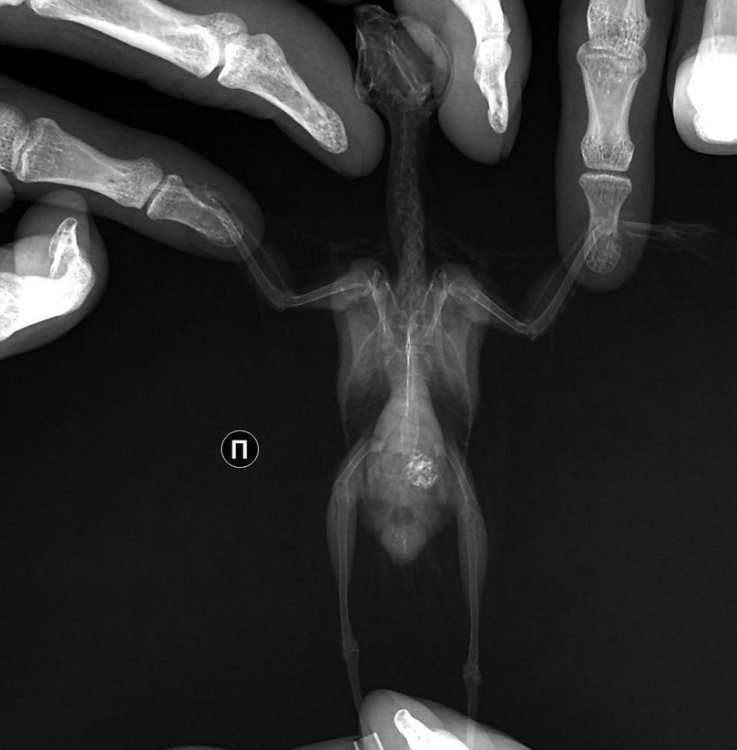

Добрый день, подскажите пожалуйста кто-нибудь похоже ли это на аспергиллез?